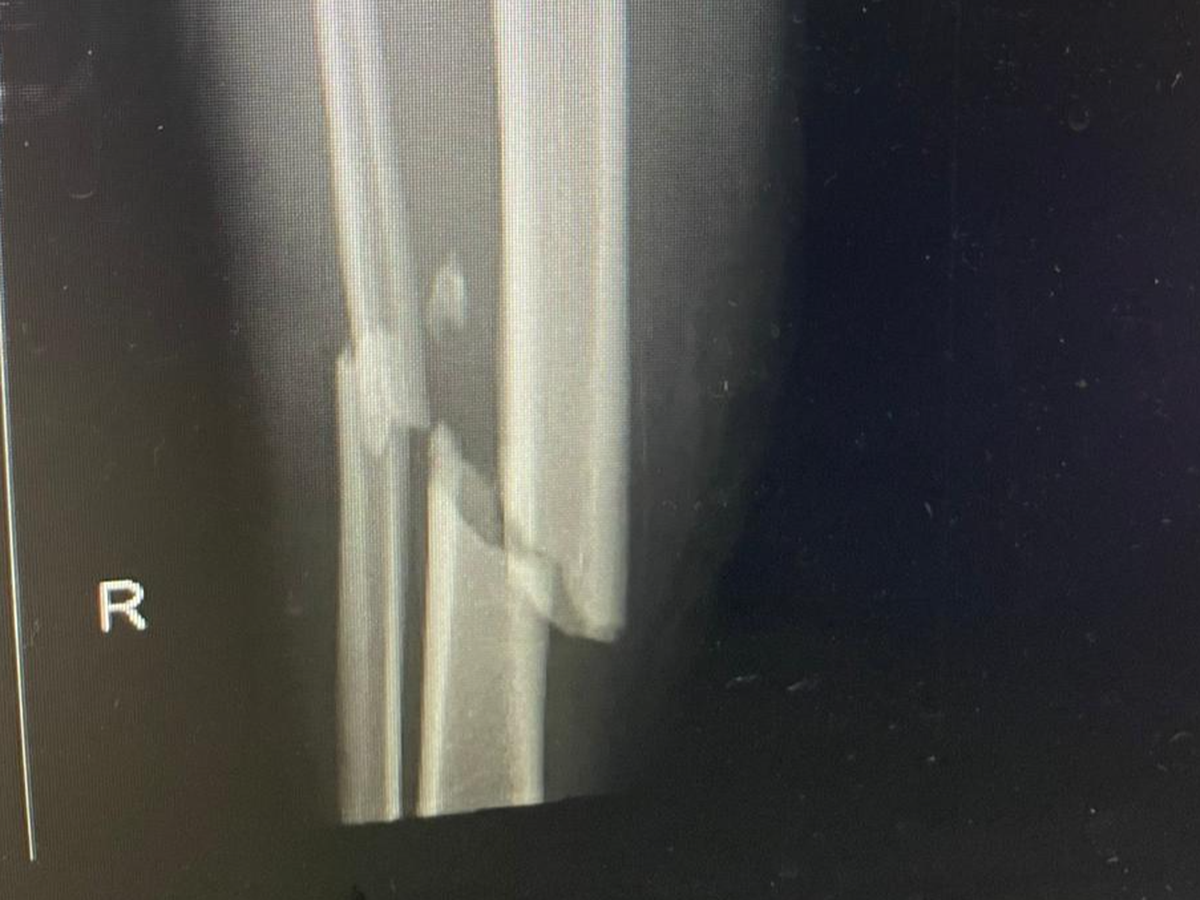

Hi. We are Park Row Rangers FC, we played in a friendly this morning, 1st June and one of our players was on the end of a tackle that has caused a broken leg. This is going to keep him out of work for multiple weeks, been told 6-8 months but that may be shorter. We are trying to raise as much funds as possible to help him out while he can't work.